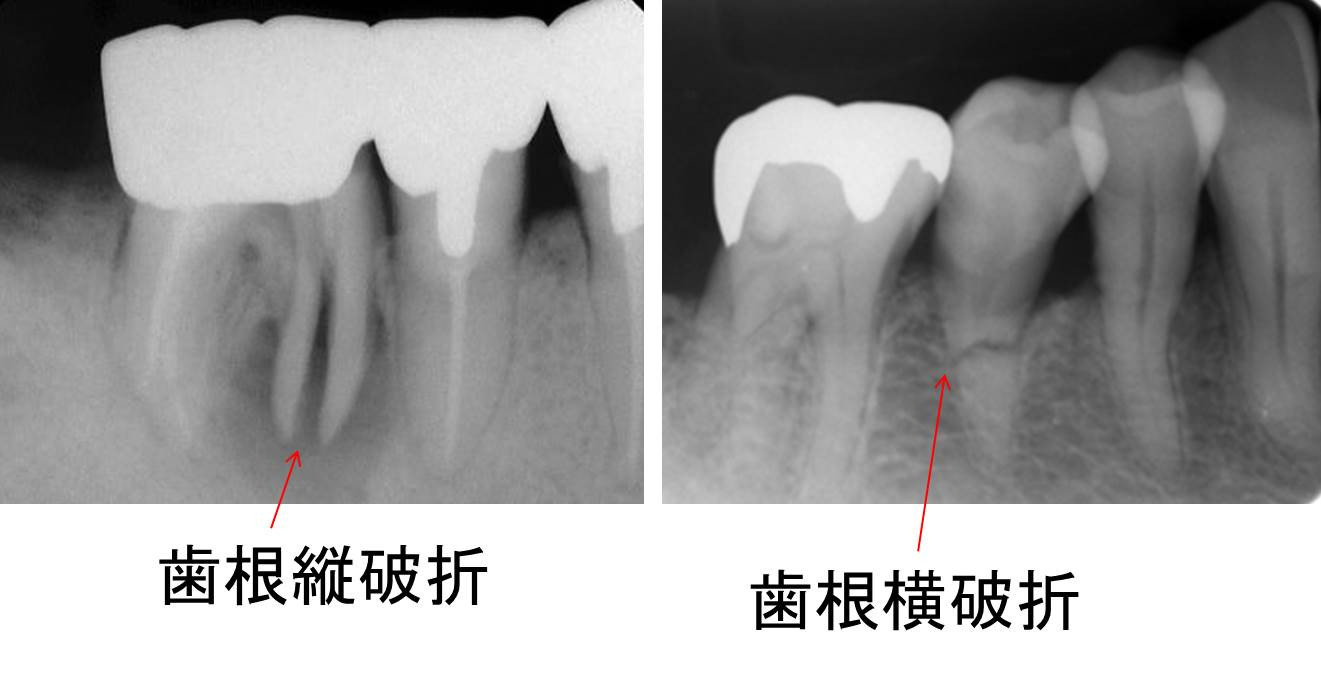

歯根破折の2症例

写真のレントゲン画像を見た場合、残念ながら2症例とも歯根破折の診断で、抜歯の診断となります。(左の写真では近心根のみの抜歯で遠心根のみ歯の半分は保存できるかもしれませんが…。)このように破折線が明確に画像診断で分かることもありますが、日常臨床では不明瞭な場合もあります。当院では、画像診断の一助として3次元CT撮影が可能なヨシダ社製のX線装置、根管内を40倍拡大できるライカ社製マイクロスコープを導入しております。根管治療が長引いている、腫れや痛みがなかなか引かない等、セカンドオピニオンも積極的に承っております歯を残したくてお困りの際は是非、グランツ歯科クリニックまでご相談ください。